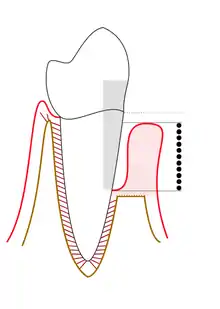

Proper use of the periodontal probe is necessary to maintain accuracy. The tip of the instrument is placed with light pressure of 10-20 grams[1] into the gingival sulcus, which is an area of potential space between a tooth and the surrounding tissue. It is important to keep the periodontal probe parallel to the contours of the root of the tooth and to insert the probe down to the base of the pocket. This results in obscuring a section of the periodontal probe's tip. The first marking visible above the pocket indicates the measurement of the pocket depth. It has been found that the average, healthy pocket depth is around 3 mm with no bleeding upon probing. Depths greater than 3 mm can be associated with "attachment loss" of the tooth to the surrounding alveolar bone, which is a characteristic found in periodontitis. Pocket depths greater than 3 mm can also be a sign of gingival hyperplasia.